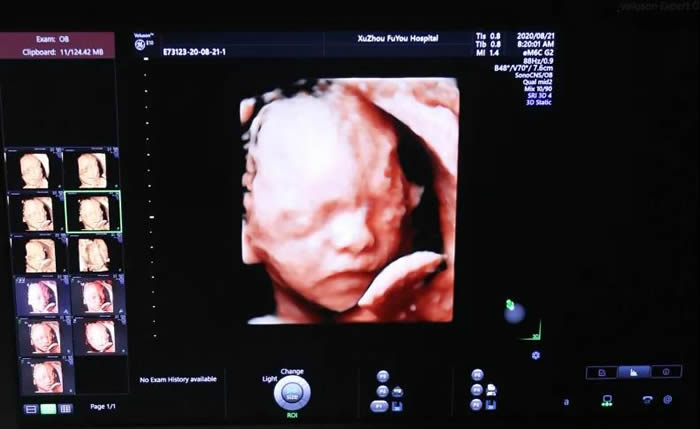

也就是準媽媽常說的四(sì)維彩超,是對胎(tāi)兒全身大結構的係統篩查

張麗主任介紹,無論是三維還是四(sì)維,都是在二維超聲的基(jī)礎上,利用計(jì)算機再處理技術達(dá)到立體模式重建的超聲診斷技術,能看到胎兒的立體圖形。“也就是(shì)說,三維彩超好比照相機,能捕捉胎兒立體靜態的畫麵,四維彩超就像攝像機,可以看到實時動態的胎兒(ér)畫麵,比如:打嗬欠(qiàn)、手舞足(zú)蹈(dǎo)的過程(chéng)。”

目(mù)前,徐州市婦幼保健院超聲醫學科擁有國際上最(zuì)高端的婦產專業四維超聲診斷儀,均屬於(yú)四維高分辨率彩超。

☆ 美國GE-Voluson E10五台,用於檢查胎兒心髒及III級(四維)、IV級彩超。